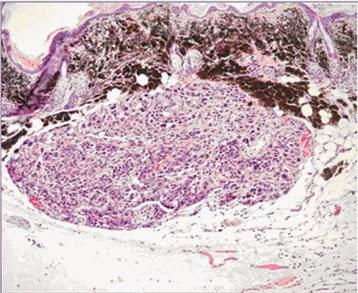

Sur cette coupe histologique d'un mélanome, les cellules tumorales commencent à envahir le derme

Source iconographique et légendaire: http://www2.cnrs.fr/presse/communique/1223.htm